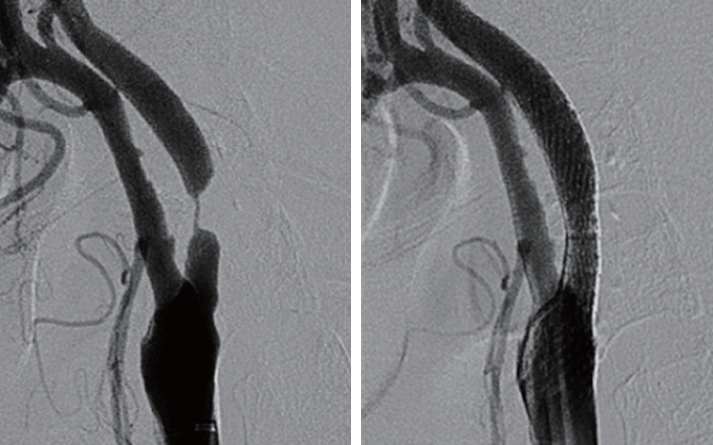

1. 뇌경색이 발생하여 응급으로 시행한 혈관조영술사진. 기저 동맥의 폐쇄가 보임.

2. 기계적 혈전제거술, 혈관성형술, 스텐트 삽입 후 혈류의 흐름이 회복됨.